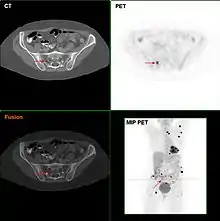

Metastatic melanomas can be detected by X-rays, CT scans, MRIs, PET and PET/CTs, ultrasound, LDH testing and photoacoustic detection.[90] However, there is lack of evidence in the accuracy of staging of people with melanoma with various imaging methods.[91]